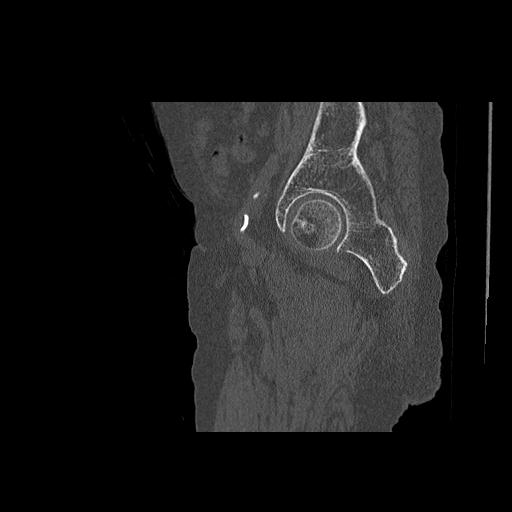

102755 1/4 2R 1/15 2R 右足関節 68歳女性 右三果脱臼骨折